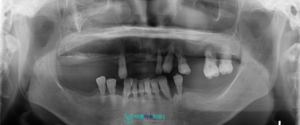

정밀한 진단을 위해

파노라마 사진을 촬영해 보았더니,

잔존 치아들 모두 심한 잇몸 질환으로 인해

예후가 좋지 않아

발치가 불가피한 상황이었습니다.

발치 후 임플란트를 진행하기에 앞서,

파노라마 사진과 3D CT 촬영을 통해

잔존 치조골의 양과 두께,

위턱의 경우 상악동막과의 거리,

아래턱 하방으로 지나가는

하치조 신경관의 위취 등

눈에 보이지 않는 해부학적 구조물까지

면밀하게 확인하였습니다.